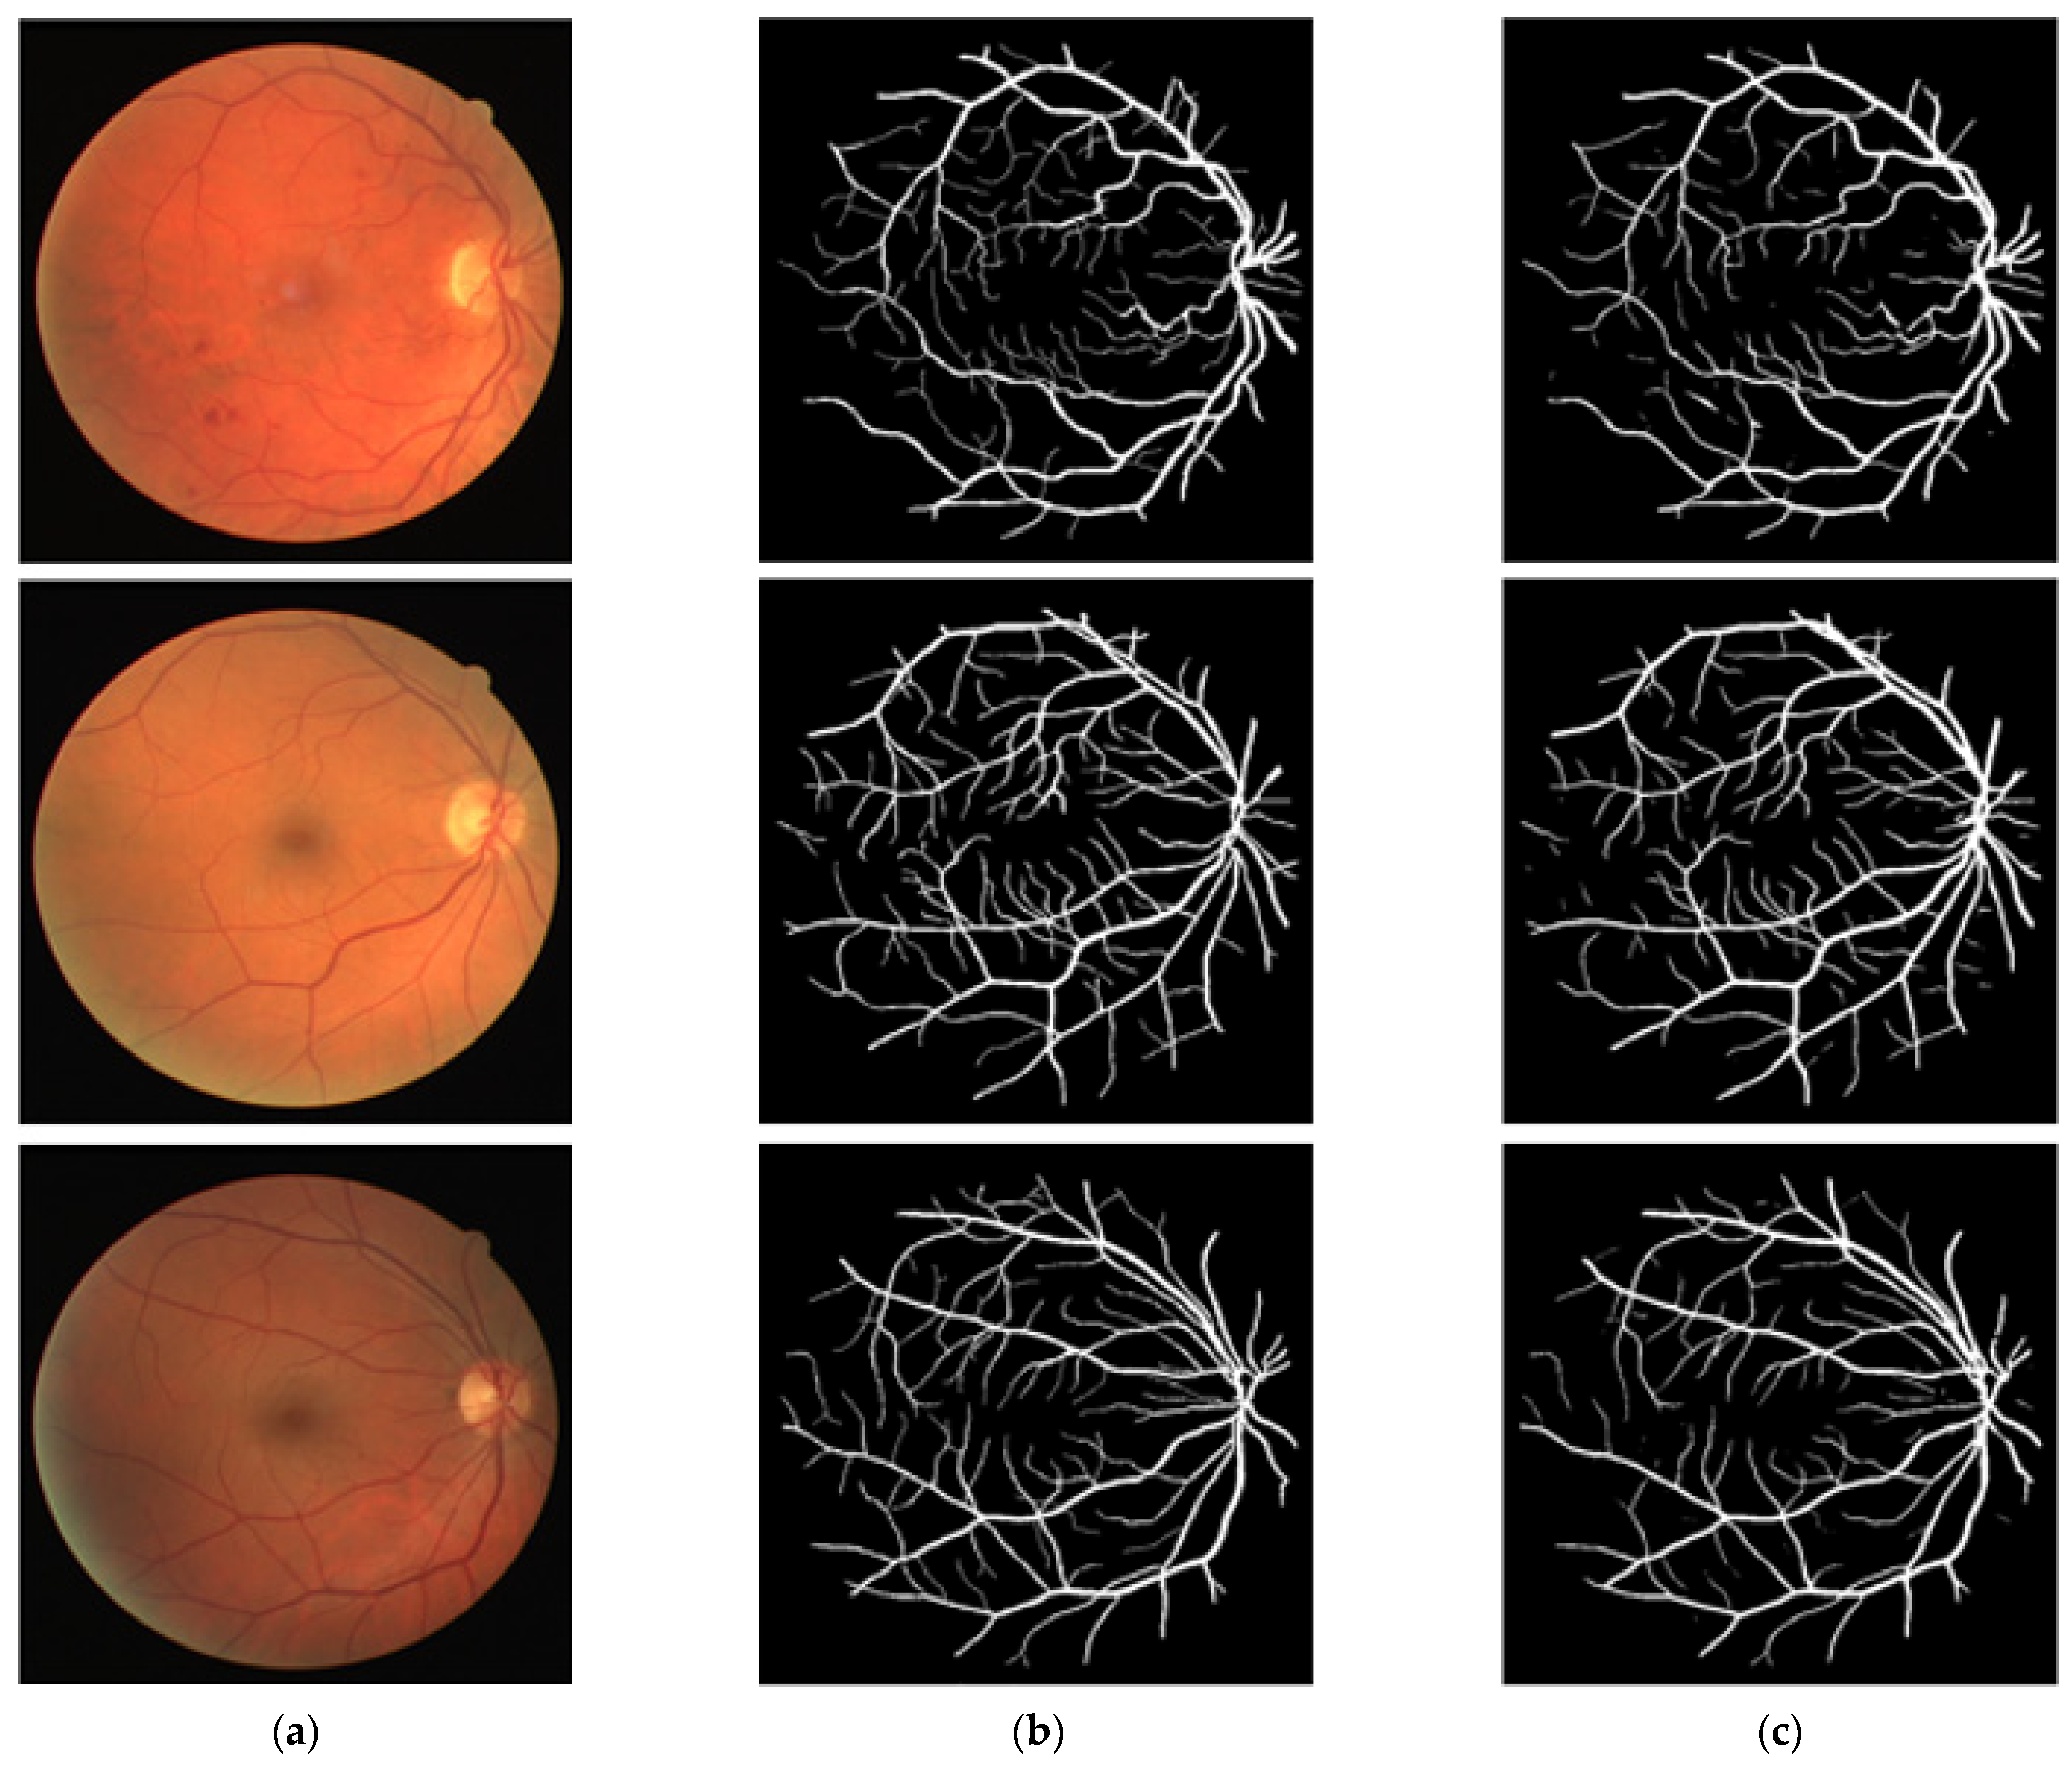

3.4. Visual Results of the Proposed Method for Vessel Segmentation

In this section, the vessel segmentation visual results are presented for the publicly available DRIVE, STARE, and CHASE-DB1 retinal image datasets. The output of the network is a binary mask that is compared with an expert annotation mask for evaluation. Figure 9, Figure 10 and Figure 11 display the visual results of the proposed method; Figure 9, Figure 10 and Figure 11 display the (a) original input image, (b) expert annotation mask, and (c) predicted mask for the proposed method.

Figure 10. Visual results of the proposed DSA-Net using the STARE dataset: (a) Original input image, (b) Expert annotation, and (c) Predicted image mask by DSA-Net.

Jpm 12 00007 g010